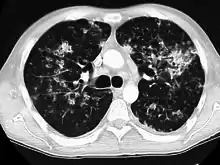

Miliary tuberculosis is a form of tuberculosis that is characterized by a wide dissemination into the human body and by the tiny size of the lesions (1–5 mm). Its name comes from a distinctive pattern seen on a chest radiograph of many tiny spots distributed throughout the lung fields with the appearance similar to millet seeds—thus the term "miliary" tuberculosis. Miliary TB may infect any number of organs, including the lungs, liver, and spleen.[2] Miliary tuberculosis is present in about 2% of all reported cases of tuberculosis and accounts for up to 20% of all extra-pulmonary tuberculosis cases.[3]

Tuberculosis of the lungs

Testing for miliary tuberculosis is conducted in a similar manner as for other forms of tuberculosis, although a number of tests must be conducted on a patient to confirm diagnosis.[4] Tests include chest x-ray, sputum culture, bronchoscopy, open lung biopsy, head CT/MRI, blood cultures, fundoscopy, and electrocardiography.[10] The tuberculosis (TB) blood test, also called an Interferon Gamma Release Assay or IGRA, is a way to diagnose latent TB. A variety of neurological complications have been noted in miliary tuberculosis patients—tuberculous meningitis and cerebral tuberculomas being the most frequent. However, a majority of patients improve following antituberculous treatment. Rarely lymphangitic spread of lung cancer could mimic miliary pattern of tuberculosis on regular chest X-ray. [15]

A case of miliary tuberculosis in an 82-year-old woman: